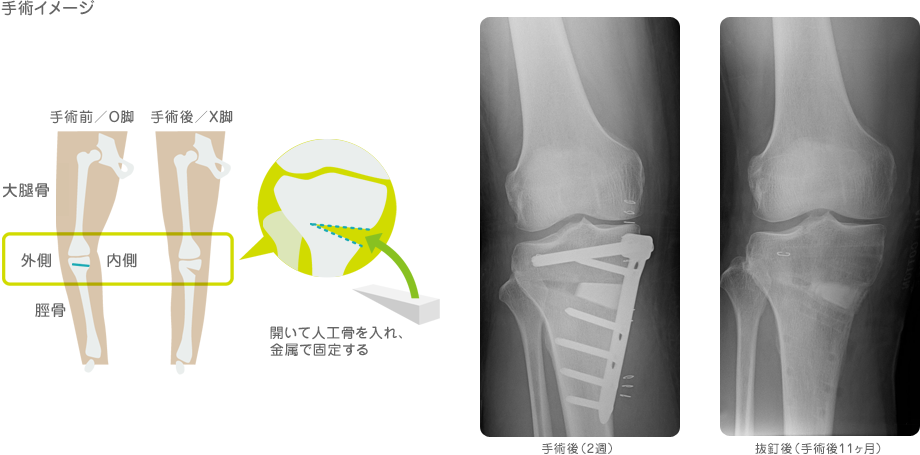

1月21日(土曜日)膝の再手術の為、最終検査に行きました。

私の膝の故障については段階的にブログにアップして参りましたが、今回は執刀医の勧めで、

高位脛(けい)骨骨切り術を受ける事にしました。

手術にあたって気がかりなのは、先生が頭を傾げながら「今までの検査データーでは

とくに悪い箇所がみられないが・・・」という言葉に今回の手術は

「・・・なんだ、対処療法か」と正直不安を感じていました・・・」

その後、先生は「念の為に断層撮影してみますか?」と言い、今日の検査になりました。

検査は微量の放射線物質(ホジトロン)を血管に注入、炎症起こしている部分を撮影するものですが撮影後、

診察で先生が膝関節の画像を見ながら

「この赤くなっている部分が炎症を起こしているので骨切り術で違いない事を確信した」

とホーッとした表情で言いましたが

一番ホーッしたのは言うまでもなく私でした。(-_-;)

こんなわけで暫く入院しますのでブログは休ませていただきます。

皆さんもくれぐれも膝関節を労わってください。

骨が完全にくっつくまで金属のプレートを骨にボルトで止めますトホホ ・・・・